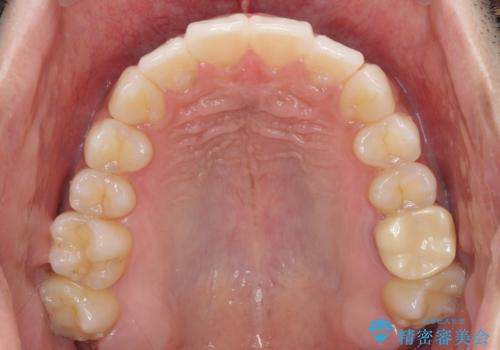

前歯のデコボコを治したい インビザライン矯正治療

- 前歯のデコボコを治したいとのことで来院された患者様です。

上下顎ともに歯列全体の後方移動とIPR(歯と歯の間を削る)によってデコボコが解消するように設計し、インビザラインにより治療を行うこととしました。

毎日22時間以上しっかりとマウスピースを装着していただいたので、スムーズに治療が進みました。歯と歯の間を削ることでうまくスペースコントロールでき、1年強で終えることができました。